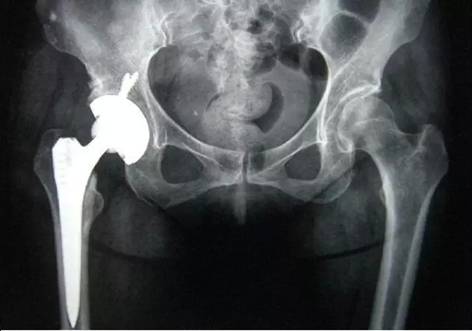

髋关节这里,有两个位置经常发生骨折,一个叫做股骨颈骨折,一个叫做粗隆间骨折。如果是股骨颈骨折,而这两个不同位置的骨折,又分别有四种常见术式:

A:人工关节置换

针对不同的年龄和身体的基础情况,人工关节置换又分为半髋置换和全髋置换,半髋置换,只换股骨头,断掉的,不要了,直接换成金属的。但是因为只置换了髋关节的一半,所以这种置换,使用寿命有限,仅适用于身体情况较差,或者预期寿命较短(<15年)的老年人。而另外一种全髋置换,不仅换股骨头,连和股骨头相对应的髋臼窝也一并置换,这种假体使用年限比单纯换股骨头要长很多,一般适用于身体情况较好,预期寿命较长的中老年人。当然,半髋置换比全髋置换手术时间短,风险小,这也是它的一个优势。